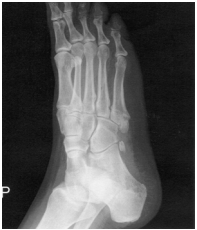

57 25 歲王小姐喜穿高跟鞋,某日逛街時,因下階梯不小心致右足 內翻受傷腫脹。醫師幫她做了檢查,發現 X 光如圖所示,則此 種骨折之形態應為下列何者?

(A)壓縮性骨折 (B)疲勞性骨折 (C)骨骺分離 (D)撕裂性骨折